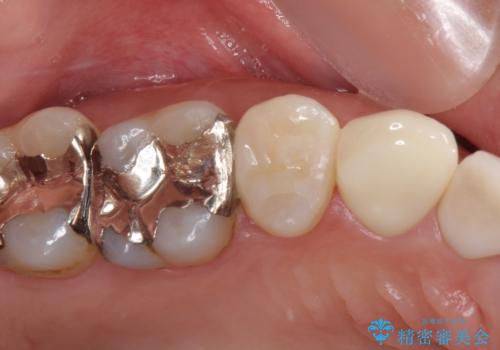

奥で目立たないことから、虫歯の再発リスクが最も低く、咬合力による歯への負担も少ないゴールドインレー(PGAインレー、白金加金インレー)にて修復治療をすることとしました。

ゴールドインレーは銀歯のインレーやセラミックインレーと比べ、「技工操作の精度が高く、適合が著しく良い」というメリットがあります。特に上の奥歯は歯科医師の操作が行いにくいため、「適合の良さ」は再治療のリスクを防ぐ上でとても重要な要素となります。

上の奥歯は金属色が見えることもないため、審美的な問題は全くありません。

咬み心地はとても良好で、全く違和感がなく、患者様には大変満足していただきました。